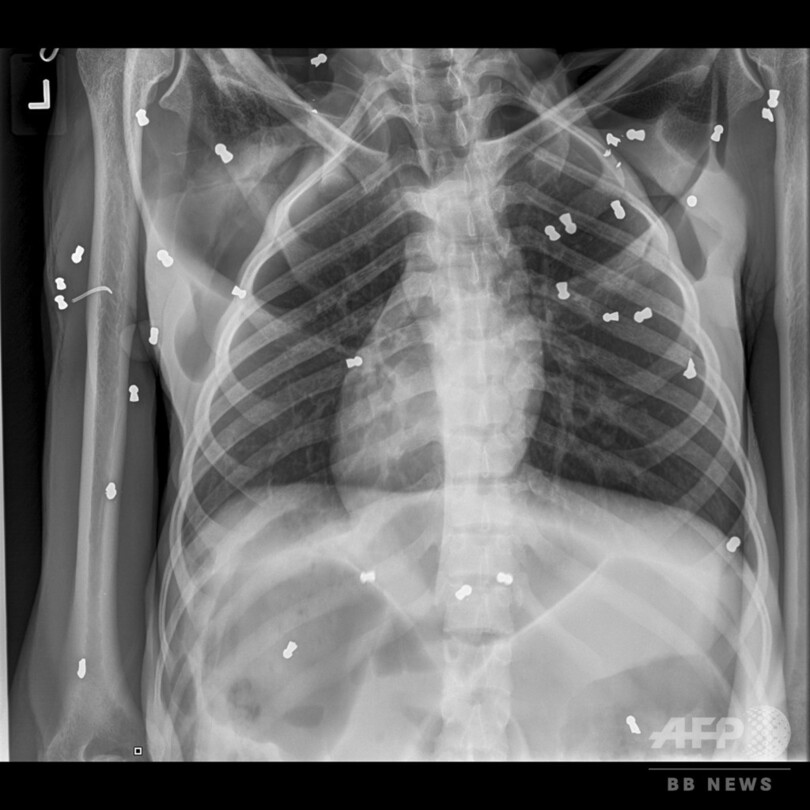

【3月17日 AFP】インドネシア当局は16日、空気銃で74発撃たれたオランウータンが徐々に回復していると明らかにした。

同国アチェ(Aceh)州当局は今月10日、村民の通報を受け、重傷を負った30歳の雌のオランウータンを発見した。オランウータンは、村民の一人が所有する農園内のジャックフルーツの木の下で死にそうな状態になっていた。このオランウータンの生後1か月になる赤ちゃんも一緒に見つかった。当局はすぐに2匹を保護したものの、赤ちゃんは栄養不良で死んだ。

同州自然資源保護事務所(BKSDA)のサプト・アジ・プラボウォ(Sapto Aji Prabowo)氏は、「農園に来たオランウータンに脅威を感じた所有者が、オランウータンを追い出そうと試みた」と説明した。保護から1週間が経過し、「ホープ(希望)」と名付けられた母親のオランウータンは少しずつ回復している。サプト・アジ・プラボウォ氏はAFPに対し、「ホープは回復してきており、食べ物も食べ始めた」と語った。